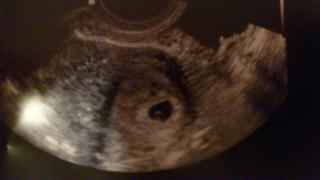

@nativanativa jeeeeeeeee machulka je tam kde ma byt aj krasnu bodecku tam vidim

@st2 vsetko je zatial v norme , uvidime o 2 tyzdne , budeme sledovat srdiecko 🙂

@nativanativa ahoooj.tak uz si pokojnejsia vsak.aj ked este nebolo srdiecko aj tak mas potvrdene ze si tehotna.je to super.pekne vidiet bodku v plodovom vajci.tesim sa s tebou.som rada ze sa ti to tiez podarilo a mohlo by sa vsetkym co uz tolko cakaju.neni ti zle?mojka bude to dievcatko to ti vravim na beton................

@nativanativa jeee, aky krasny obrazok...dokonca vidno uz aj zltkovy vacok...vypada to velmi krasne a nadejne...🙂)

@nativanativa jeeeeeeeeej no krasa 🙂 aj ja si chcem buduci tyzden takyto krasny obrazok domov doniest 🙂